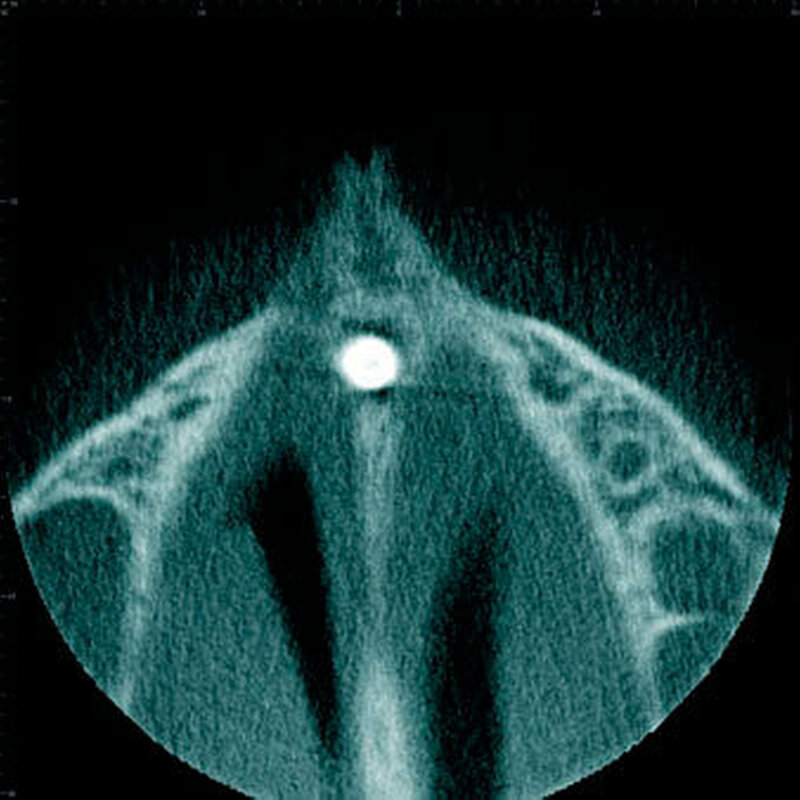

Überzählige Zähne werden nach ihrer Lage im Zahnbogen und auch aufgrund ihrer Morphologie eingeteilt. Basierend auf der Lage unterscheidet man bei überzähligen Zähnen zwischen Mesiodens (Oberkiefer median), zwischen den zentralen Inzisiven (Abbildungen 5 und 6), einem zusätzlichen Schneidezahn (zentral oder lateral), Eckzahn, Prämolar (Abbildung 7), Paramolar und Distomolar (Abbildungen 8). Mesiodentes werden am häufigsten dia- gnostiziert, wobei Prozentsätze zwischen 38,8 Prozent bis 86,3 Prozent der überzähligen Zähne in der Literatur zu finden sind [Salcido-García et al., 2004/38,8 Prozent, Fernández Montenegro et al., 2006 /46.9 Prozent; Mossaz et al., 2014/48.5 Prozent; Ferrés-Padró et al., 2009/53.2 Prozent; Schmuckli et al., 2010/75 Prozent; Rajab Hamdan 2002/83.2 Prozent; Liu et al., 2007/86.3 Prozent]. Überzählige Prämolaren und seitliche Schneidezähne sind die zweithäufigste Gruppe der überzähligen Zähne. Überzählige Eckzähne, Paramolaren und Distomolaren dagegen gelten als eher selten [Rajab Hamdan, 2002; Salcido- García et al., 2004; Liu et al., 2007; Ferrés-Padró et al., 2009; Schmuckli et al., 2010; Mossaz et al., 2014]. Einzig eine Spanische Gruppe [Fernández Montenegro et. al., 2006] berichtete, dass Paramolaren und Distomolaren insgesamt relativ häufig seien (18 Prozent, beziehungsweise 5,6 Prozent). Überzählige Zähne kommen im Ober- und Unterkiefer vor, wobei sich überzählige Schneidezähne in der Regel im Oberkiefer, überzählige Prämolaren sich dagegen eher im Unterkiefer befinden [Fernández Montenegro et al., 2006; Ferrés-Padró et al., 2009; Mossaz et al., 2014]. Überzählige Molaren wiederum treten normalerweise im Oberkiefer auf [Cassetta et al., 2014; Kaya et al., 2014].

Bei überzähligen Zähnen werden vier morphologische Typen unterschieden: konisch (Abbildung 9), tuberkulär (höckerförmig; Abbildung 10), überzählige Zähne mit identischer Zahnform (Abbildung 11) und Odontom (Abbildung 12) [GARVEY et al. 1999]. Der konische überzählige Zahn ist ein kleiner, zapfenförmiger Zahn und zudem der häufigste Fall im bleibenden Gebiss [Rajab Hamdan 2002, Liu et al. 2007, Gündüz et al., 2008; Ferrés-Padró et al., 2009; Hyun et al., 2009; Schmuckli et al., 2010; Mossaz et al., 2014]. Er kommt oft zwischen den oberen zentralen Schneidezähnen vor und entwickelt sich gleichzeitig zur Wurzelbildung der bleibenden Schneidezähne. Konische überzählige Zähne führen meist nicht zu einer Durchbruchstörung oder -behinderung der zentralen Schneidezähne. Tuberkuläre, überzählige Zähne sind größer als der konische Typ und besitzen einen zusätzlichen charakteristischen Höcker oder Tuberkel der Zahnkrone. Sie kommen oft gepaart vor und liegen in der Regel palatinal der oberen mittleren Schneidezähne. Im Gegensatz zu konischen überzähligen Zähnen brechen die meisten tuberkulären nicht in die Mundhöhle durch und es kommt nicht selten zur Durchbruchstörung oder -behinderung der zentralen Schneidezähne [Mason et al., 2000; Minguez-Martinez et al., 2012]. Überzählige Zähne mit identischer Zahnform sind Zähne, welche vom eigentlichen Zahn in der Lage (also in der Zahnreihe gelegen) und Form nicht zu unterscheiden sind.